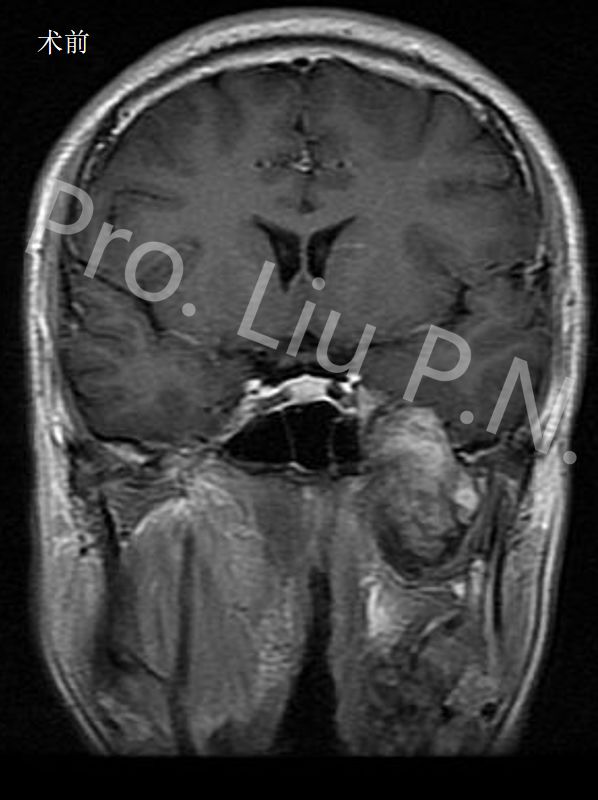

十、经筛-翼突入路手术案例

--左海绵窦神经鞘瘤

![]()